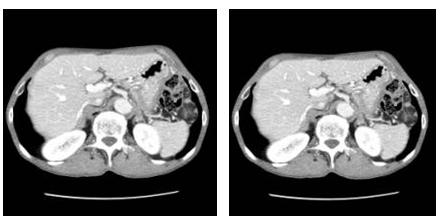

식도암에서 흉부 및 복부 전산화 단층촬영

전산화단층촬영(CT)은 X-선을 우리 몸에 투과 시킨 후 얻어진 신호를 컴퓨터로 계산하여 신체의 단면을 영상으로 나타내는 검사입니다. 식도암에서는 흉부 및 복부 전산화단층촬영(CT)을 시행함으로써 식도암의 위치와 주위 조직으로의 침범 여부, 흉강 및 복강 내 림프절 전이의 판정(수술 전 병기 결정), 흉강 및 복강내의 원격 전이(림프절이 아닌 신체기관에의 전이) 판정 등에 이용되며, 식도암 이외에 동반된 흉부 및 복부질환의 진단에도 도움이 되며, 수술 후의 합병증을 확인하거나 항암화학요법의 반응 정도를 확인하는 데에도 많이 쓰입니다.